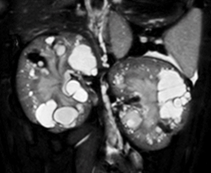

多発性嚢胞腎は、ネコで最も一般的な遺伝性腎疾患です。腎臓に多数の嚢胞が形成されることが特徴であり、時に肝臓や膵臓にも嚢胞が発生します。腎臓に形成された嚢胞は加齢とともに数と大きさを増し、腎実質の圧迫により腎機能が低下します(図1)。ネコ多発性嚢胞腎の多くの症例でPKD1遺伝子エクソン29にナンセンス多型(注1:chrE3:g.42858112C>A)が検出されることが2004年にLyonsらによって報告され、ネコの多発性嚢胞腎の原因と考えられています(図2)。この変異体はストップコドンとなるため、それ以降の翻訳が停止し、C末端側のタンパク質が約25%喪失します。この変異体がホモ接合体の場合、胎生致死となるため、多発性嚢胞腎のネコは必ずヘテロの多型を有することが知られています。これまでに海外における複数の疫学調査が報告されていますが、日本での大規模な疫学調査は行われていませんでした。また、PKD1遺伝子エクソン29のナンセンス多型(chrE3:g.42858112C>A)以外の遺伝子多型が存在するのかについては、国内・海外ともに報告がなく不明でした。